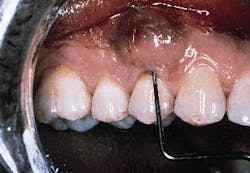

The defect subsequent to flap elevation can be seen in photograph #2. Calculus is evident on the buccal root surface.

Photograph #2: Subsequent to flap elevation a large piece of calculus is observed on the facial aspect of tooth #5.